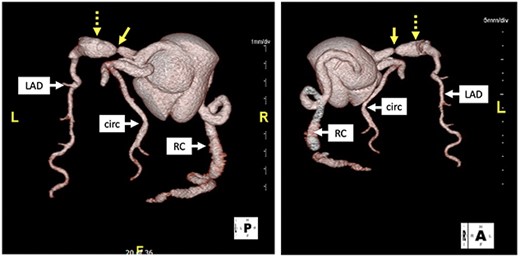

His initial troponin was not elevated although the electrocardiogram showed new ST depressions in the medial precordial leads and subsequent troponins were elevated. He was transferred to our institution and underwent left heart catheterization which demonstrated a right dominant circulation with ectasia of the right coronary artery, a fusiform aneurysm of the left anterior descending coronary artery (LAD) and a generous-sized left circumflex coronary artery (Fig. 1). There was a 99% stenosis of the LAD with post-stenotic dilatation up to 13 mm with gradual normalization over the course of the remainder of the vessel. An echocardiogram showed a left ventricular ejection fraction of 35% without valvular pathology. Percutaneous coronary intervention (PCI) was thought to be a poor option because the distal portion of the stent would not oppose the wall of the vessel but be ‘floating’ in the aneurysmal portion of the artery pre-disposing thrombus formation. Therefore, in anticipation of operative intervention, a computed tomography scan was done to further define the anatomy. The scan demonstrated extensive wall thickening and contour irregularity suggestive of diffuse coronary arteritis (Fig. 2). The study also showed a dilated main pulmonary artery up to 46 mm and an aberrant right subclavian artery coming off the distal aortic arch and passing behind the esophagus.

Computed tomography with 3D reconstruction. Solid yellow arrow points to tight stenosis in the left anterior descending and dotted yellow arrow points to post-stenotic aneurysm.